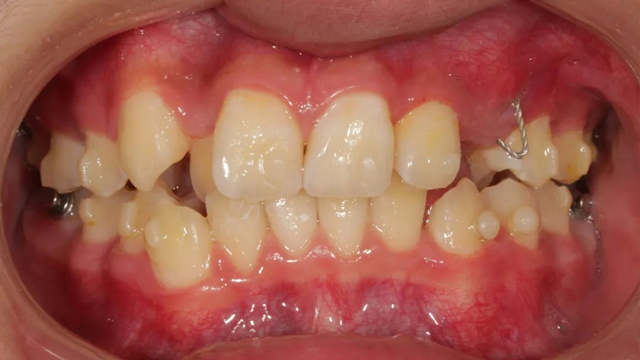

“我給這個病例取了一個可愛的名字,叫‘拯救迷路的小虎牙’。”據王亞楠醫生介紹,這是一個典型的集多種問題于一身的青少年矯治病例,有替牙障礙、牙列不齊,還伴有個別牙反頜以及先天性多生牙的問題。除了技術難度,患者作為未成年人能否嚴格遵醫囑佩戴隱形牙套,也是醫生需要考慮的問題。

“孩子當時11歲,家長發現牙齒長得比較亂,就趁放暑假帶過來看了。經過檢查,發現他的問題并非單純的牙列不齊,還有一顆恒牙無法自行萌出,也就是存在替牙障礙,需要做牽引治療,因此整個治療周期相對較長,從2021年8月開始到2024年9月結束。”

2021年8月(矯正前口內照)